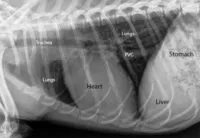

Labeled X-ray of a normal heart

A labeled X-ray highlighting heart position in a normal feline chest.